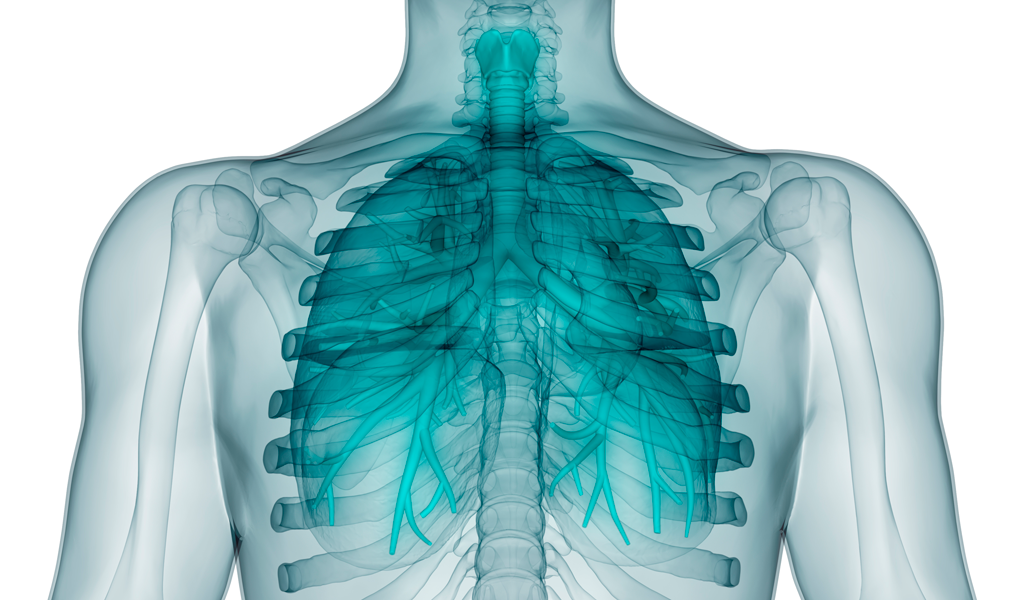

- La sarcoidosis es una enfermedad sistémica de causa desconocida que en casi el 90% de los pacientes se caracteriza por inflamación granulomatosa del pulmón. La presencia de granulomas no caseificantes puede ser en cualquier órgano, más comúnmente los pulmones y los ganglios linfáticos intratorácicos.

Hasta el 50% de los pacientes presentan síntomas respiratorios, como dificultad para respirar, tos seca y dolor en el pecho.

- Los datos radiográficos se clasifican por etapas.

- Etapa radiográfica I: sólo adenopatía hiliar bilateral.

- Etapa radiográfica II: adenopatía hiliar y afectación del parénquima.

- Etapa radiográfica III: sólo invasión del parénquima.

- Etapa radiográfica IV: es la que muestra cambios fibróticos avanzados, principalmente en los lóbulos superiores.

- La etapa radiográfica III suele manifestarse en la radiografía por infiltrados reticulares difusos, infiltrados focales, sombras acinares, nódulos y, rara vez, cavitación.

- En menos de 10% de los pacientes se identifica un derrame pleural.

- La biopsia transbronquial del pulmón tiene un rendimiento alto (75 a 90%), en especial en personas con evidencia radiográfica de afectación del parénquima.